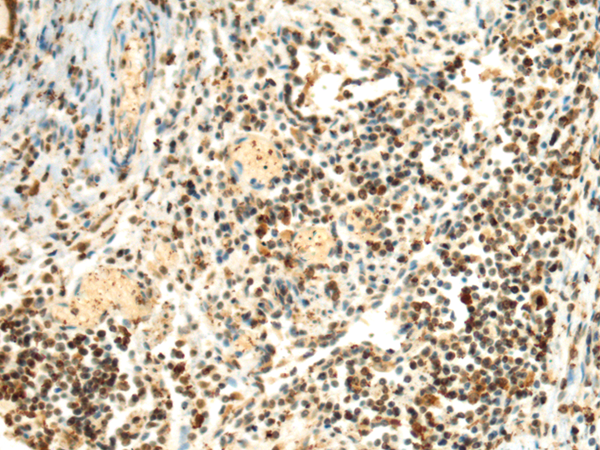

The image is immunohistochemistry of paraffin-embedded Human prostate cancer tissue using P03422(SEPHS1 Antibody) at dilution 1/85. (Original magnification: ×200) |

The image is immunohistochemistry of paraffin-embedded Human lung cancer tissue using P03422(SEPHS1 Antibody) at dilution 1/85. (Original magnification: ×200) |